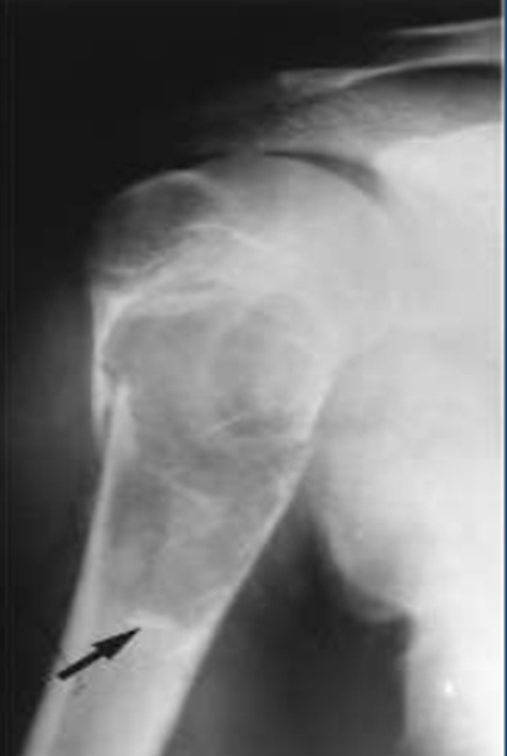

Lesão de Hill Sacks

Fratura por compressão da cabeça umeral